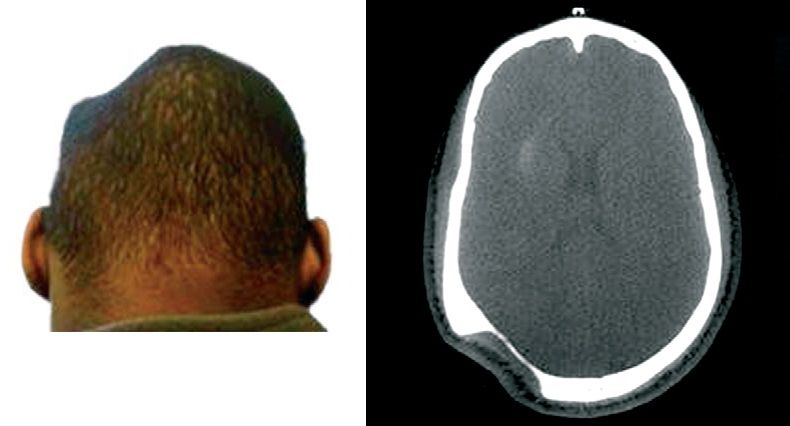

CT of the head showed massive destruction of bone, within a well defined area. A technetium-99m methylene diphosphate bone scan showed increased metabolic activity at the edges of the area.

These findings were consistent with Gorham’s disease – a rare idiopathic disorder in which one or several bones are destroyed and replaced by connective and vascular tissue. Gorham’s disease of the ribs or thoracic vertebrae can lead to chylothorax and life-threatening respiratory failure. Radiotherapy and surgery are the main therapeutic options.